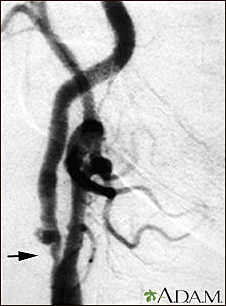

Carotid stenosis - X-ray of the right artery